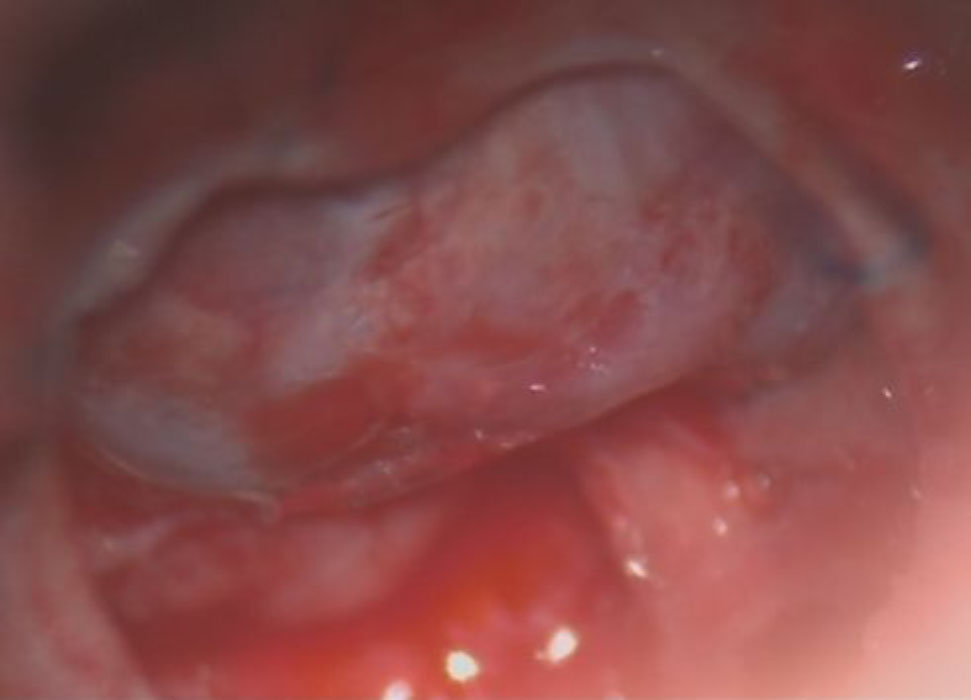

706

'25年12月

80代

右頭頂葉腫瘍

頭蓋内腫瘍摘出術

No.’25_108 手術前1

No.’25_108 手術前2

No.’25_108 摘出 前

No.’25_108  摘出 中

No.’25_108 摘出 後